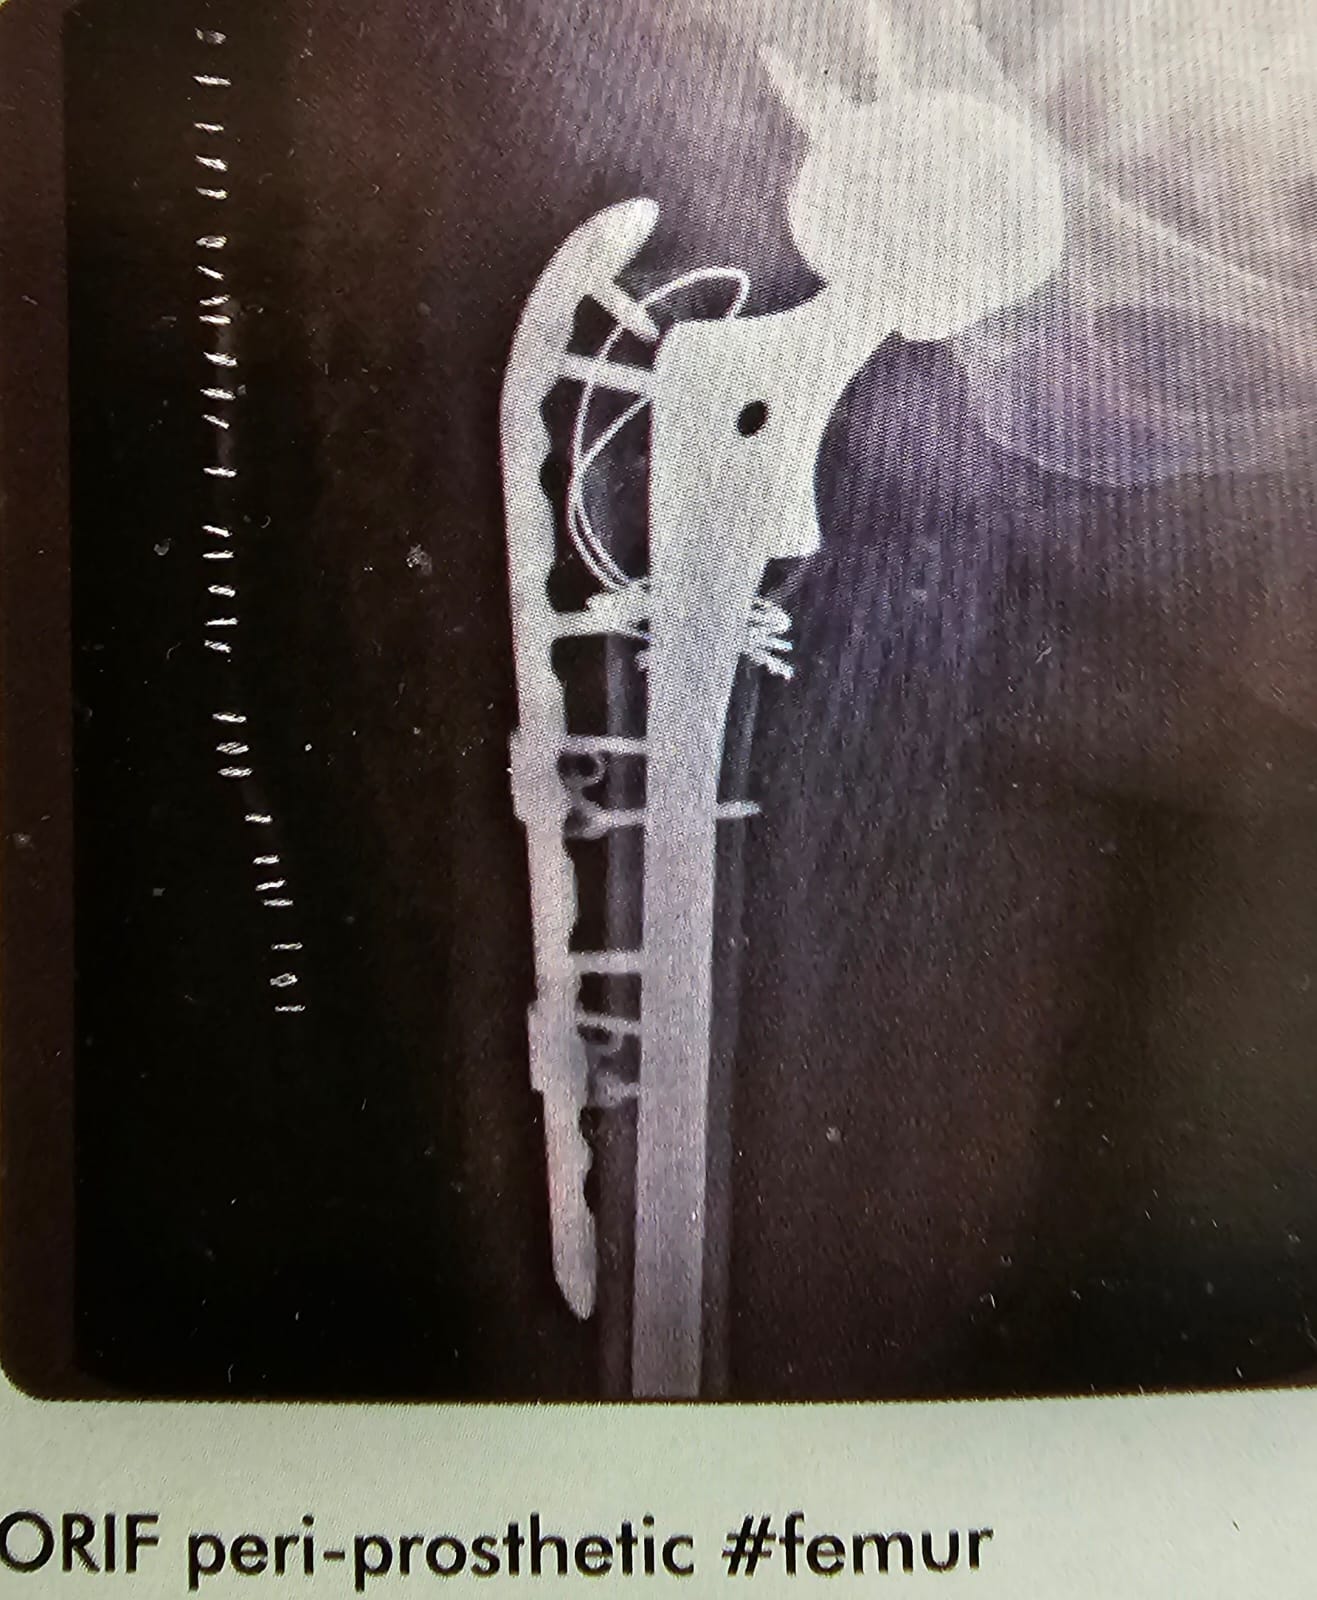

ORIF – Peri Prosthetic # Femur

This is the case of peri prosthetic fracture of the sub trochanteric region of the femur after THR was done in a un cemented hip. She managed with trochanteric plate, with circulage wires and screws through the plate